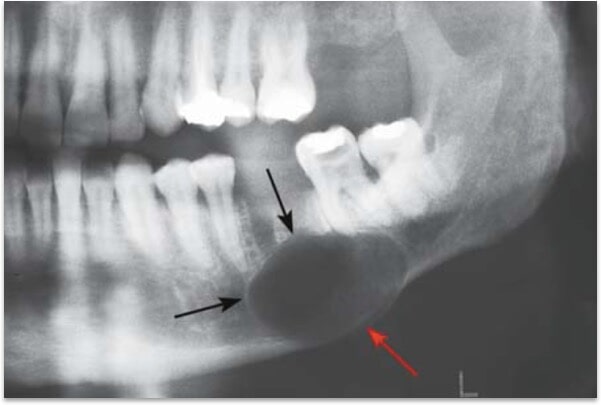

נגעים

פתולוגיים בעצמות הלסתות כוללים – זיהומים ממקור דנטלי או אחר, ציסטות ממקור

התפתחותי או זיהומי, גידולים שפירים או ממאירים, ביטויים גרמיים למחלות סיסטמיות,

מחלות ונגעים של מפרקי הלסת ועוד. נגעים פתולוגיים בלסתות לרוב מתגלים באופן אקראי בצילום, או במצבים שמופיעים סימפטומים כגון נפיחות או כאבים. מומלץ אם כן לבצע בדיקת רופא שיניים תקופתית אחת ל-6 עד 12 חודשים כולל צילומים. במצבים מסוימים (כגון נוכחות שיני בינה כלואות) מומלץ לבצע צילום פנורמי, בו לרוב ניתן לבצע אבחון ראשוני של פתולוגיות בלסתות. במידת הצורך יפנה רופא השיניים או הכירורג לביצוע CT או MRI. לרוב כרוך הטיפול בנגעים בלסתות בהוצאה כירורגית. במצבים מסוימים יהיה צורך בטיפול מקדימים להליך הכירורגי ובשחזור הלסת לאחריו.

ציסטה בלסת התחתונה